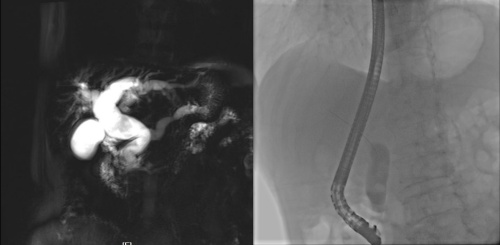

2月26日,刘鹏主任医师带领手术团队成功为黄爷爷实施手术,手术全程用时不到一小时,顺利取出多颗结石,其中直径较大的结石为1.0cm,再次造影,胆总管内负影消失,手术非常成功。